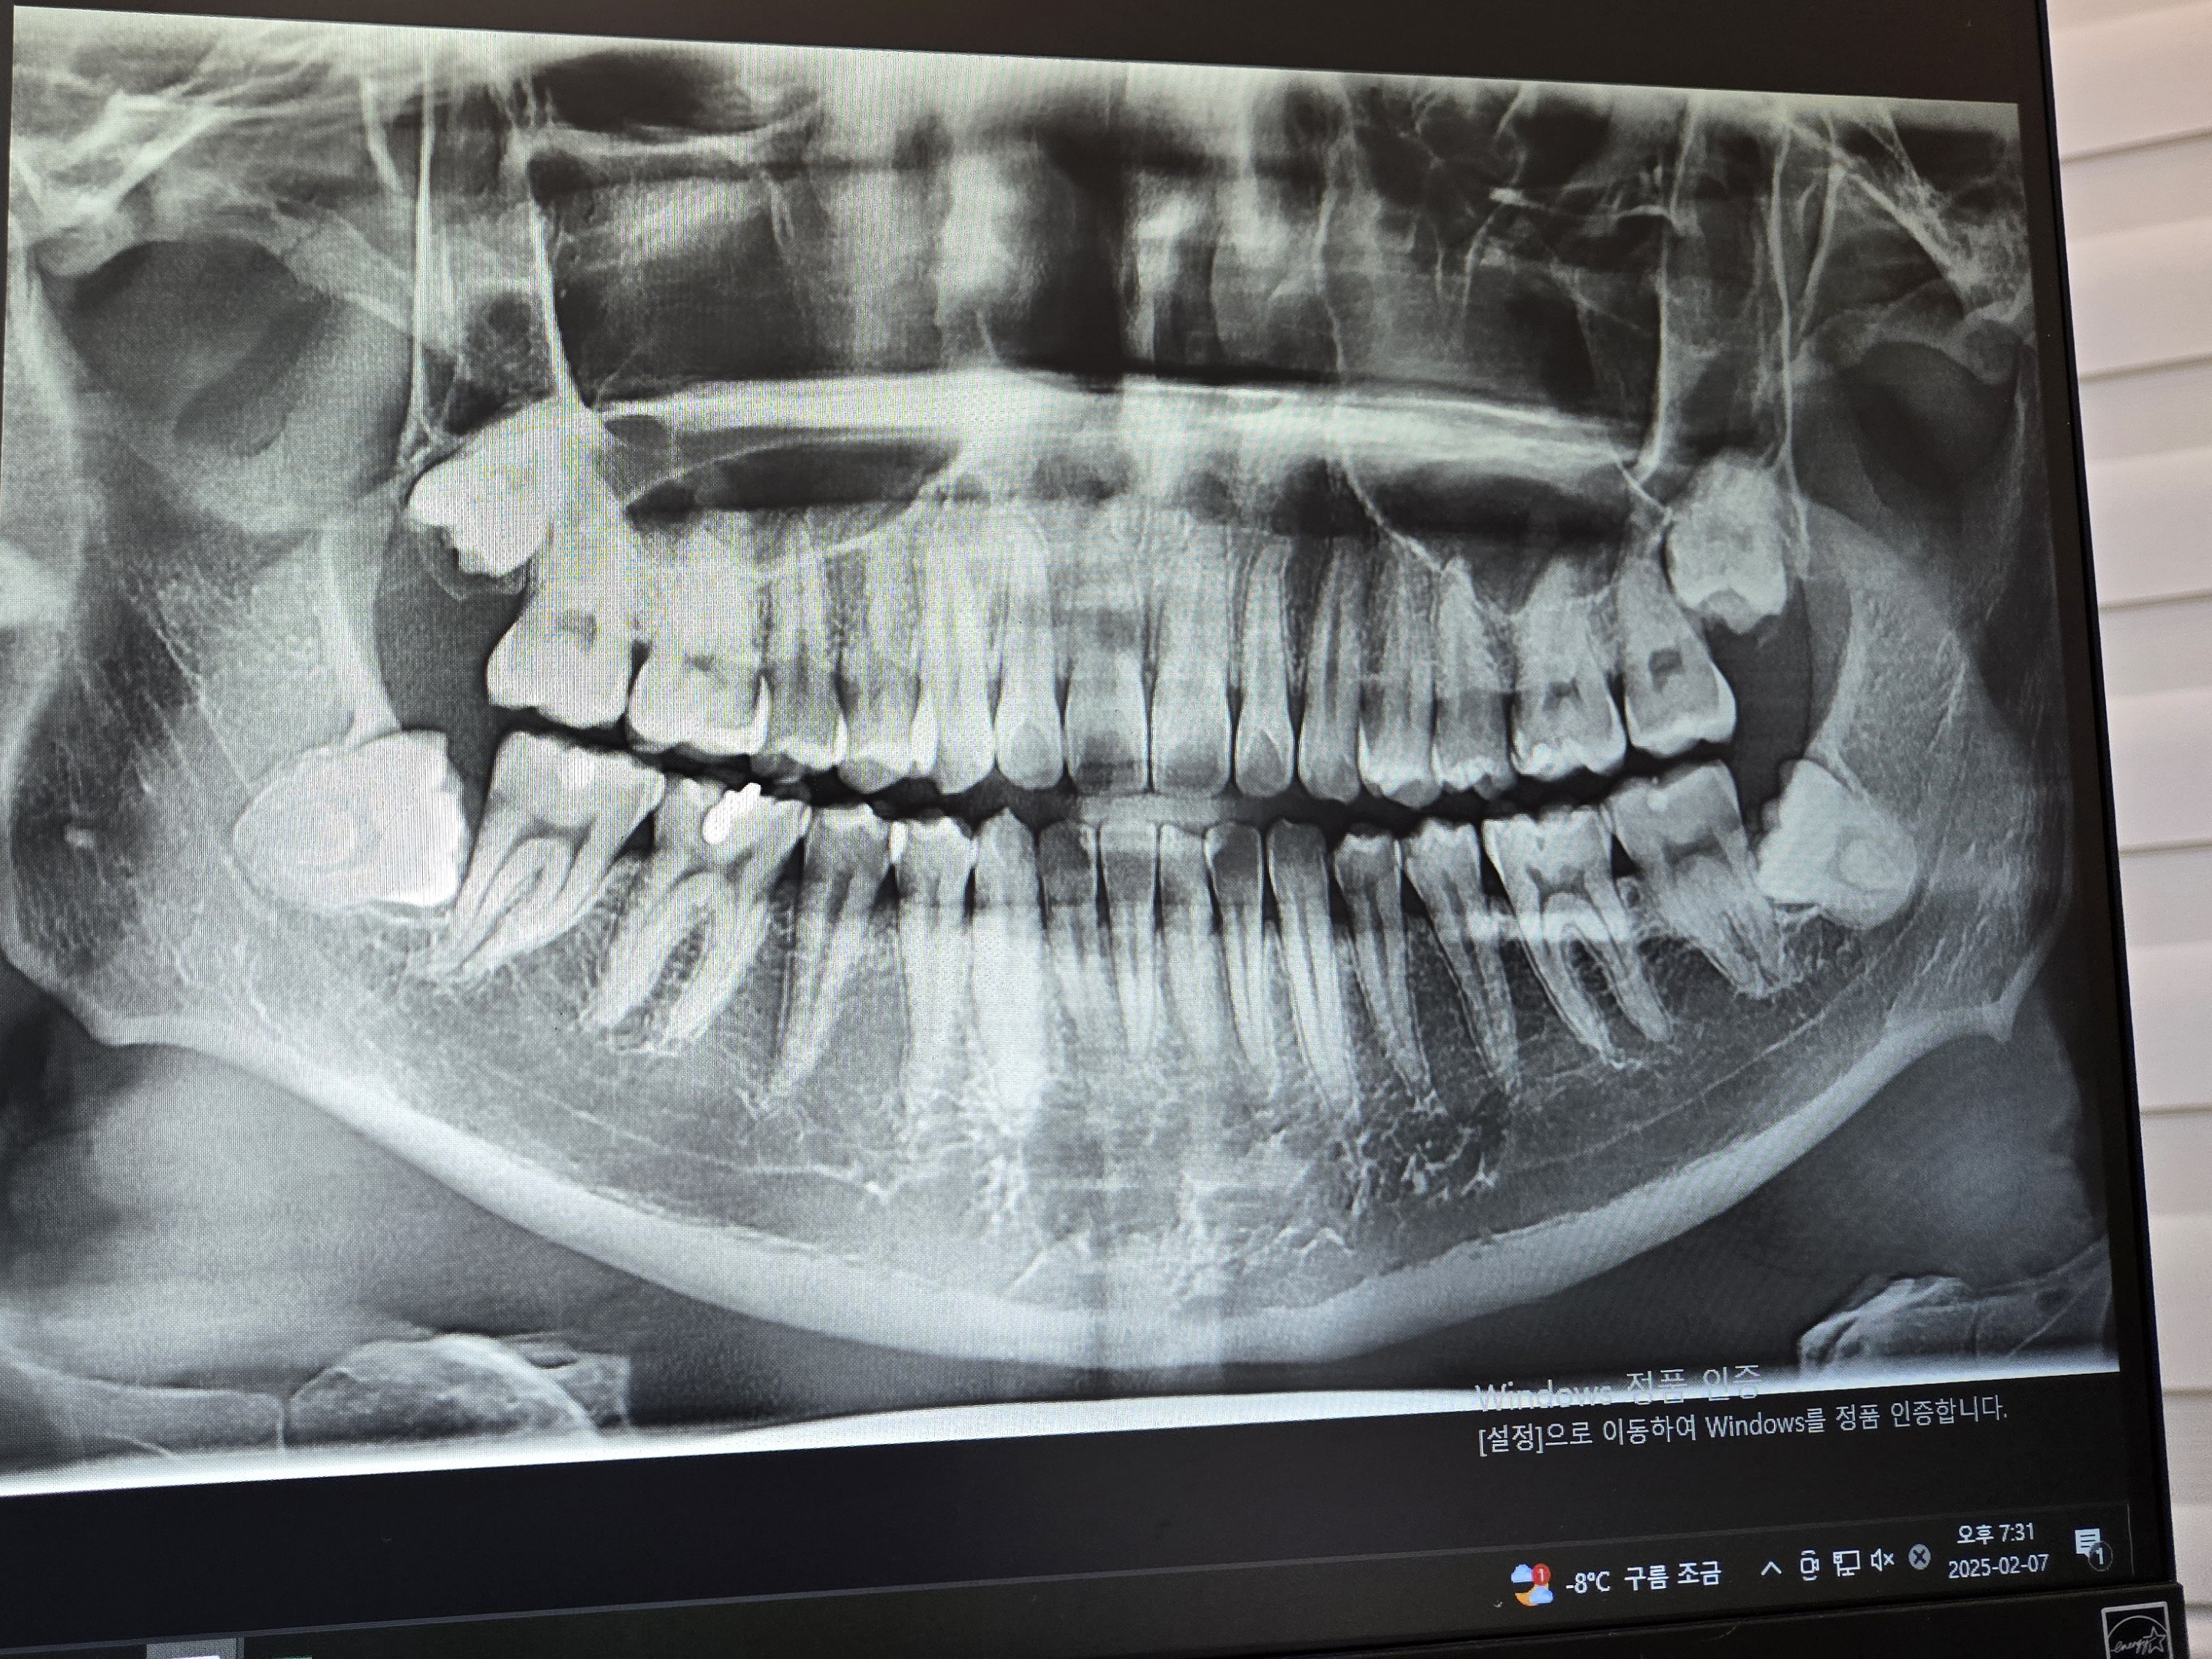

최근 치과에서 가서 찍은 사진을 참고하자면, 완전 매복 사랑니로서 아주 이쁘게 누워계셨다.

그리고 엑스레이상으로 아래 사랑니들이 신경을 통과하는 위치라 CT까지 찍어서 신경을 최대한 건들이지 않는 방향으로 뽑아야 한다고 CT까지 찍고 귀가를 했습니다.

치과의사 선생님 왈 CT를 찍어보니 사랑니가 신경을 누르고 있어서 발치하다가 신경에 손상이 갈 수도 있다. 발치 후 다음날에도 마취가 풀리지 않은 것 같은 느낌이 들면 즉시 치과를 방문해달라는 주의 말씀은 해주셨다.